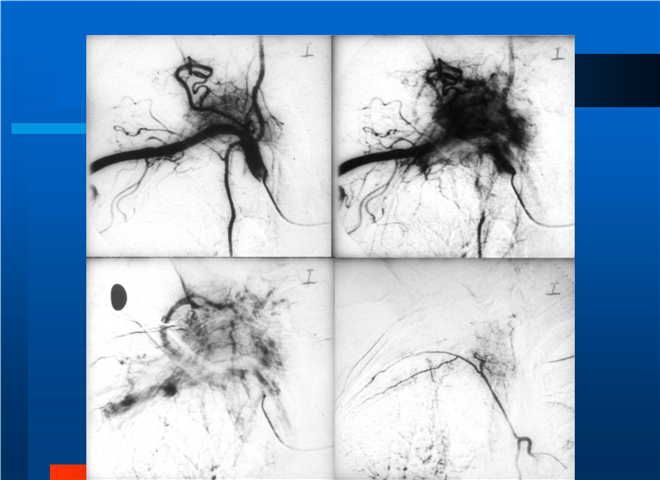

04_肺癌的介入治疗